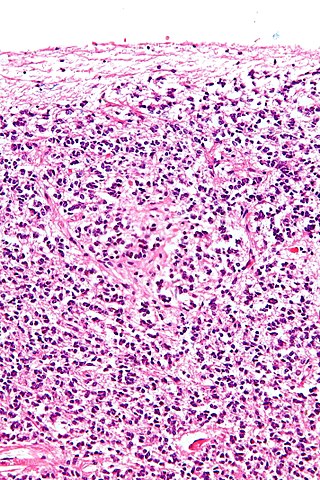

La característica principal de las glándulas endocrinas es que sus células están organizadas en forma de “cordones” o folículos.

Las glándulas con organización interna tipo cordón son las más comunes y se distinguen por el hecho de que sus células se “apilan” alrededor de capilares sanguíneos, hacia los que liberan sus productos cuando el estímulo adecuado las alcanza.